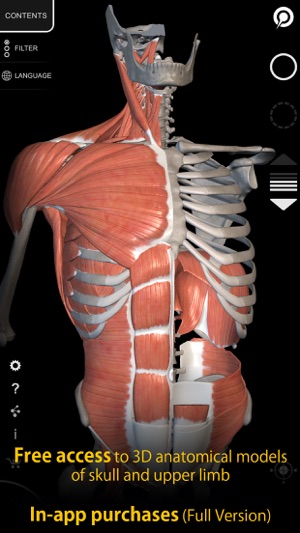

Free access to the following 3D anatomical models:

Skeleton (skull, trunk and upper limb)

Ligaments and muscles (upper limb)

In-app purchases to unlock all body regions.

The musculoskeletal system has been reconstructed in 3D, you can rotate and zoom in on each model and observe in detail from any angle.

• The muscles are grouped into layers, from the superficial to the deepest

• Visualization of the muscle layers in multi or single mode

• Possibility to hide every single bone or muscle

• Filter feature to hide or display every system